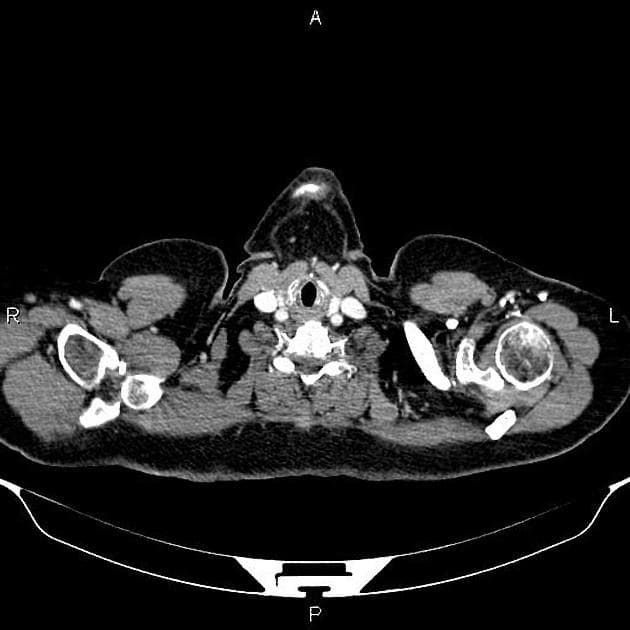

Ung thư ống mật trung tâm và đặt ống dẫn lưu qua da dưới hướng dẫn chụp cắt lớp vi tính (PTC)

- Gan không có hình ảnh xơ gan (cirrhosis), có hình ảnh giãn rộng ống mật trong gan lan tỏa, với hiện tượng tắc đột ngột tại các ống gan chính bên trái và bên phải ở vùng cửa gan (hilar region), nơi có khối tổn thương xâm lấn, giới hạn không rõ (ill-defined mass).

- Khối này trên hình ảnh cộng hưởng từ:

- Tín hiệu hơi tăng trên hình ảnh trọng T2 (slightly high signal intensity on T2WI)

- Hạn chế khuếch tán (restricted on DWI)

- Giữ thuốc tăng quang trên các thì muộn (retained contrast on delayed phases).

- Ung thư ống mật trung tâm (central cholangiocarcinoma)